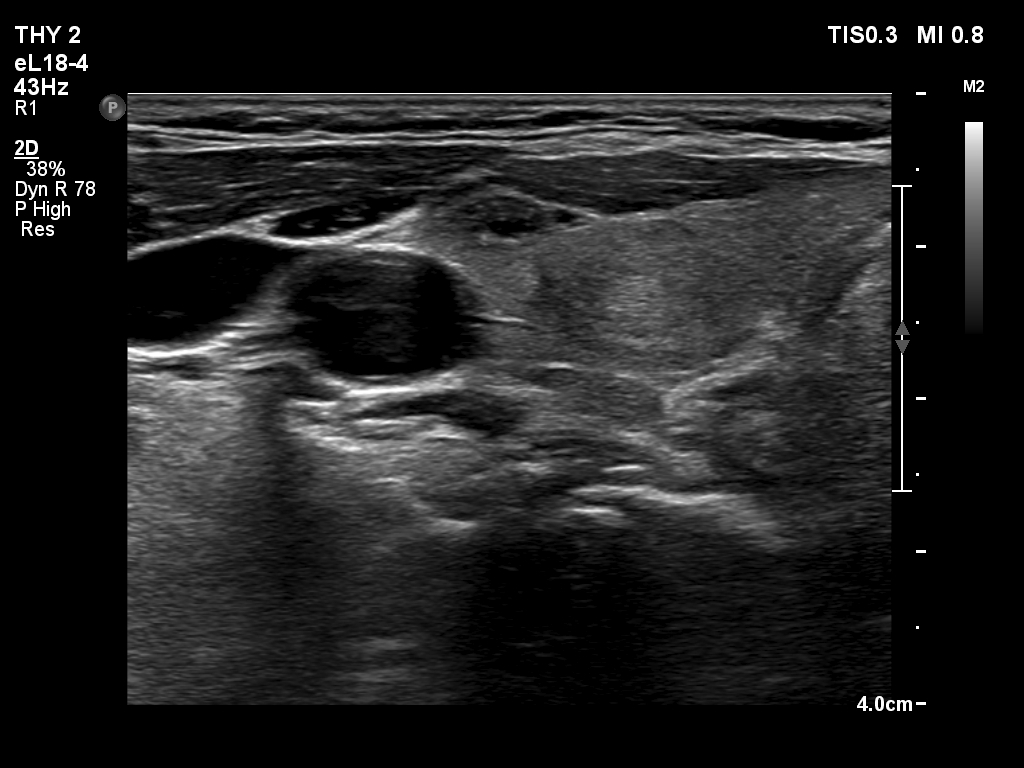

Right lobe, longitudinal scan

Lower part of the right lobe, another transverse scan. There are several more discrete lesions.